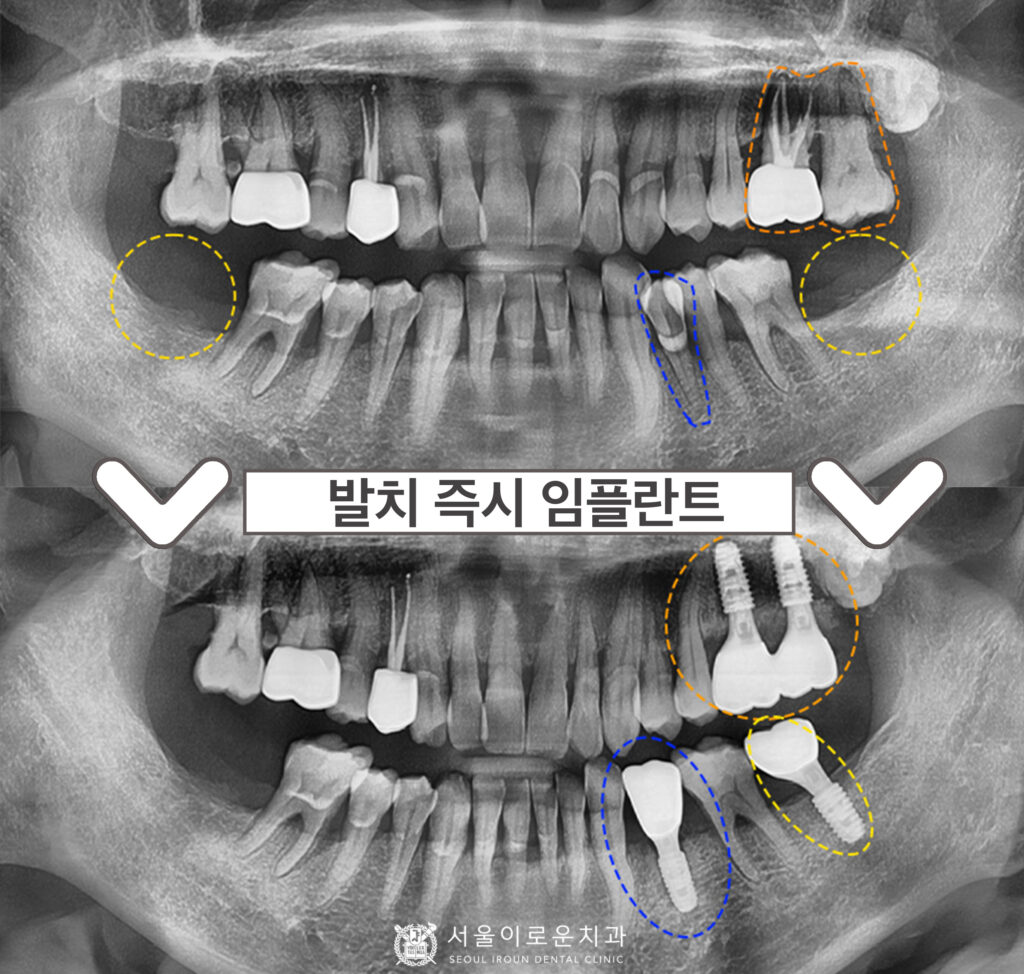

본.원에 처음 오셨던 60대 남성분의 사진입니다.

왼쪽 위에 큰 어금니를 보시면 과거 타원에서 신경치료를 했으나

뿌리 끝에 염증이 생긴 것을 알 수 있었습니다.

바로 옆에 위치한 어금니도 상태가 좋지 않았는데요.

치주염이 많이 진행되어

치아가 심하게 흔들리는 상태였습니다.

또한, 아래 양쪽 큰 어금니가 1개씩 상실된 상태였습니다.

4개의 치아를 발치한 뒤,

뼈이식을 동반한 임플란트를 바로 식립하여

촬영한 x-ray 사진입니다.

기존에 상실되어 없었던

왼쪽 아래 큰 어금니 부위에도

임플란트를 추가로 식립하였습니다. ^^

환.자분의 경우 치주염이 많이 진행된

상태로 잇몸뼈가 상당수 흡수되어

골이식을 동반하였는데요.